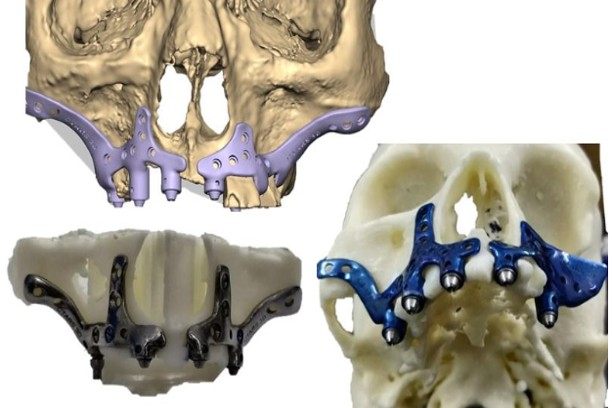

Zygomatic / Pterygoid Implants

Anchored in the cheekbone for patients with limited upper jaw bone.

PATIENT SPECIFIC IMPLANTS